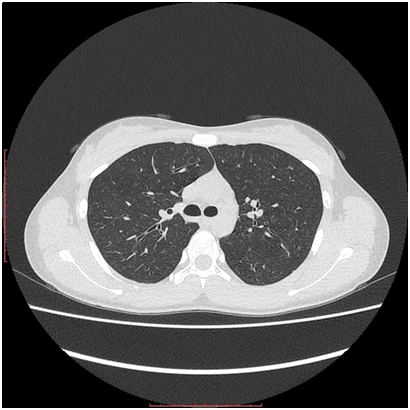

8. Chest CT: diffuse micro-focal centrilobular dissemination in the pulmonary tissue of both lings. Linear bridles with pleuropulmonary adhesions in S4 of the right ling (Figures 3 & 4) and in S8 of the left lung. Trachea and bronchi are viewed until sub-segmental, bronchial walls are thickened, with normally aerated lumens. Mediastinum and roots are well structured. Chest lymph nodes not enlarged. Diaphragm is normally situated, free fluid in the pleural cavities not seen. Pericardial layers are thin. Peripheral lymph nodes are not enlarged.

Figure 3 Chest CT. Diffuse micro-focal “ground-glass” changes in both lungs.

Figure 4 Chest CT. Diffuse micro-focal “ground-glass” changes in both lungs, and linear pleuropulmonary fibrosis in the middle lobe of the right lung.

And the last but not least, lung involvement in both cases was also relatively modest and torpid. In case 2 only chest CT demonstrated micro-focal “ground-glass” changes, characteristic for the early stage of the disease, or for the torpid course,13-17 while the plain chest X-ray examination failed to reveal any pathology features, even though the latest studies (both X-ray and CT) were performed 6 months after the disease onset. Such discrepancy between CT and Chest X-ray data is well described in the literature.13 In case 1 plain chest X-Ray also did not show any changes, despite severe iron deficient anemia, suggesting subclinical hemorrhage into alveolar spaces. Unfortunately we were not able to perform chest CT in that particular case, but we presume that diffuse “ground-glass” foci might be confirmed by CT, if it would be done.